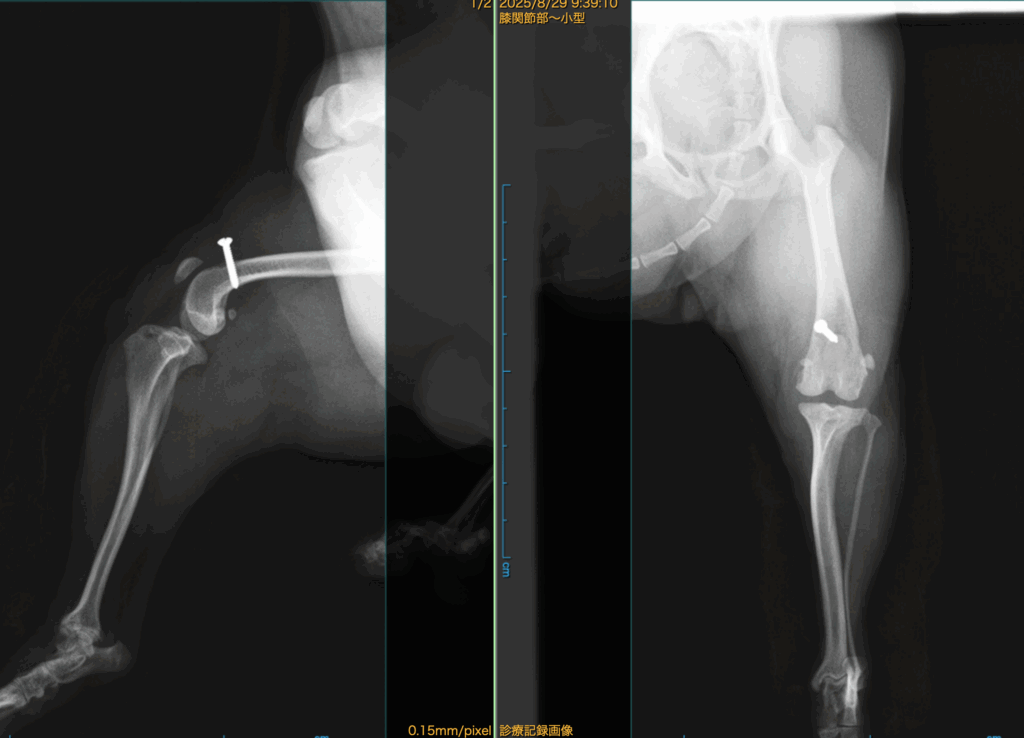

「チワワのMPLGrade3 Pre Xray」

「術中所見:大腿骨滑車部位の軟骨損傷、欠損」

この部位で膝蓋骨(パテラ)は容易に脱臼します。

この部位の脱臼を防ぐ為には滑車溝を形成(深く)しても脱臼してしまうでしょう。。